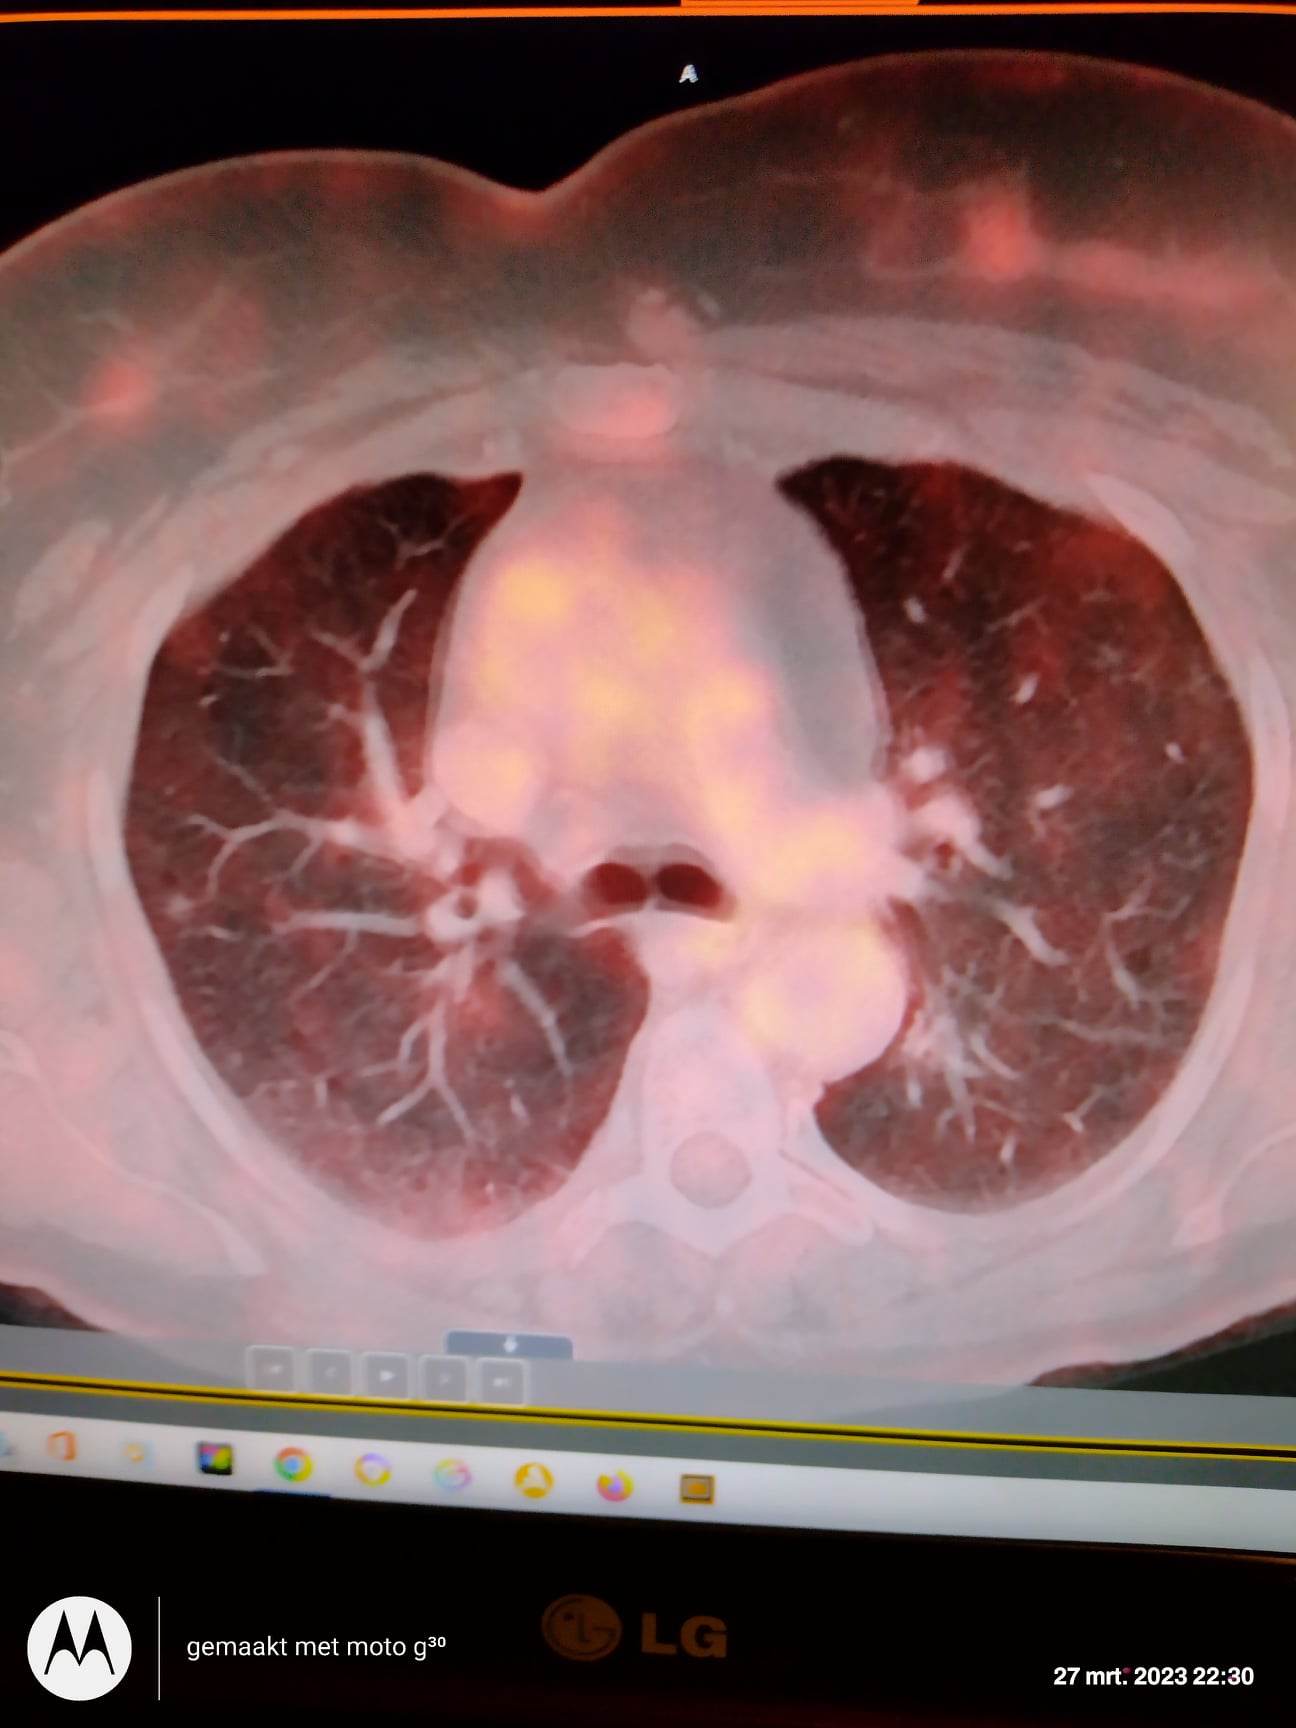

Er werd bij mij een longfoto genomen , ct-scan , longspoeling , 9 stukjes weefsel van de long (biopsie) en pet-scan genomen . 10 leukocyten per microliter , galactomannan negatief , gramkleuring negatief , matglas ; alveolitis : fibrose of consolidatie , nodulaire longletsels bilateraal , verspreide matglas infiltraten , emfyseem / cystische longafwijkingen , verdacht letsel in long snel bloedend , enkele haardjes van discreet verhoogde activiteit verspreid over de beide longen , beiderzijds accentuatie van de linguale tonsillen reactief inflammatoir , haard van matig verhoogde activiteit lateraal , matig verhoogde metabolisme in de nodule lateraal in bovenkwab rechterlong en iets minder postenobasaal bovenkwab links , verhoogde FDG stapeling in verspreide matglas noduli beiderzijds , wazig begrensde nodule in linkerbovenkwab mogelijk met beperkte scissurale doorgroei , geexcaveerde verwondingen van 9mm in rechter onderkwab met een matglazen halo , atelectasis (ingeklapt longweefsel) , dunwandig extraverend letsel in rechter onderkwab . In longspoeling waren ook ontstekingscellen te zien . In een vorig bericht stelde ik al de vraag van ct-scan van 5 jaar geleden waar er een fors imponerende hili , mogelijk opgebouwd uit vaten , cave op basis van lymfoadenopathie . Ik heb ook livedo verspreid over gans mijn lichaam . In bloed staan lymfocyten te hoog . Gisteren om de uitslag bij longarts om de resultaten te bespreken en hij zei me dat dit alles komt door inademen van toxische stoffen . Sigaretten roken . Dat een tumor niet is uitgesloten maar heel onwaarschijnlijk lijkt omdat het zich voordoet in beide longen . Volgens hem komt een tumor in beide longen niet voor . Hij stelde voor om 4 maand te wachten en dan opnieuw ct-scan te doen en zien of alles hetzelfde is gebleven of dat het erger is geworden . Moet ik mij neerleggen bij deze uitspraak ? Lijkt me onmogelijk dat dit alles komt door 12 sigaretjes per dag te roken ? Alsook toen hij in het begin de ct-scan foto's zag maakte hij direct afspraak voor longspoeling en biopsie want er mocht geen tijd verloren gaan , zei hij . En nu ineens zo van , we gaan 4 maand wachten ? Klopt niet ! Hier foto bijgevoegd van pet-scan . Ik heb er nog veel maar kan hier maar 1 foto toevoegen .

De bevindingen op de PET-scan doen vermoeden dat er sprake is van ontstekingsverschijnselen verspreid in de longen en de lymfeklieren. Dat kan van alles zijn. De patholoog zal daar in de biopten zeker goed gekeken hebben.

Aanvankelijk is waarschijnlijk ook aan kanker gedacht. Daar moet je bij rokers natuurlijk altijd rekening mee houden. De biopten hebben geen kankercellen laten zien en de verspreiding van de verhoogde uptake op de scan past daar eigenlijk ook niet bij.

Waar die ontstekingsverschijnselen door veroorzaakt zijn is blijkbaar niet duidelijk en een eenduidige diagnose kon men er zo te zien niet op stellen.

Veel meer mogelijkheden voor aanvullende diagnostiek zijn er nu niet en nu aannemelijk is gemaakt dat het geen kanker is mag je inderdaad wel een paar maanden afwachten om te zien hoe het beeld zich ontwikkelt. En in de tussentijd zorgen dat het niet erger wordt door alle prikkels te vermijden die ontstekingen kunnen verergeren (inderdaad het roken, maar ook viezigheid op het werk of in huis, geneesmiddelen etc.)!